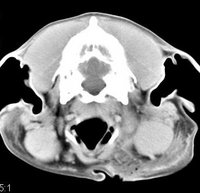

imágenes de TC en el perro | ||||||||||

ejemplo de imágenes de TC en el perro. Nótese la celulitis en la región parotídea izquierda | ||||||||||